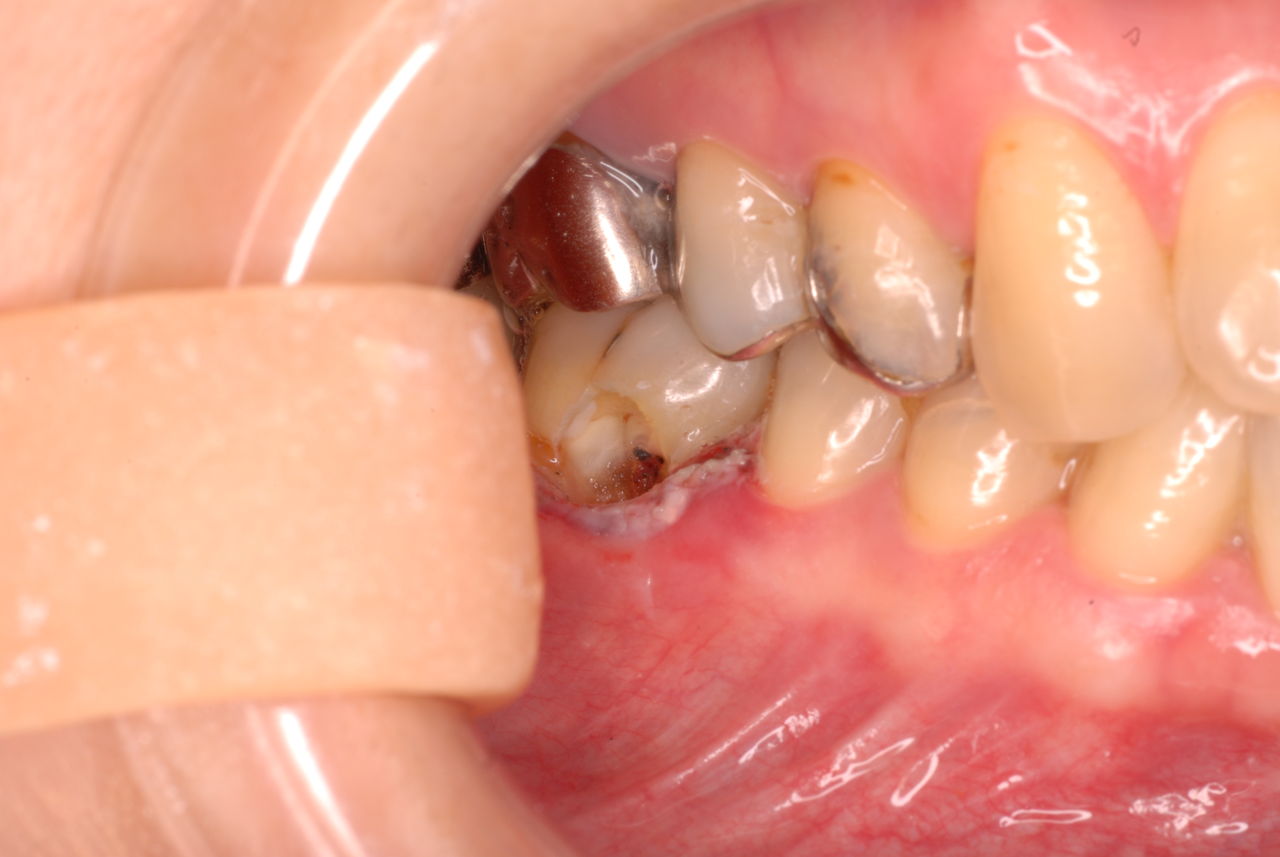

相談しても“問題無い”の説明だけだそうです。調べたところ歯周病は進行しているし、奥歯の大きい歯2本ずつ計4本はしっかり噛んでいないのです。よく噛めないというのはそのことのようでした。これを矯正的に元に戻すことはできない訳ではありませんが、時間と手間がかかるのは間違いないことです。

歯を削らないといいましても結局歯の間を削りスペースを確保したそうですから、何らかの歯に対する傷害はしているのです。それは虫歯や歯周病を起こしやすい理由にもなりますからこれからも要注意なのです。二年間という貴重な時間を費やしていますから患者本人は大変だったと思います。そして二年間を要したならば更に二年間動かないようにするための入れ歯やマウスピースを装着し続けなければいけないのです。